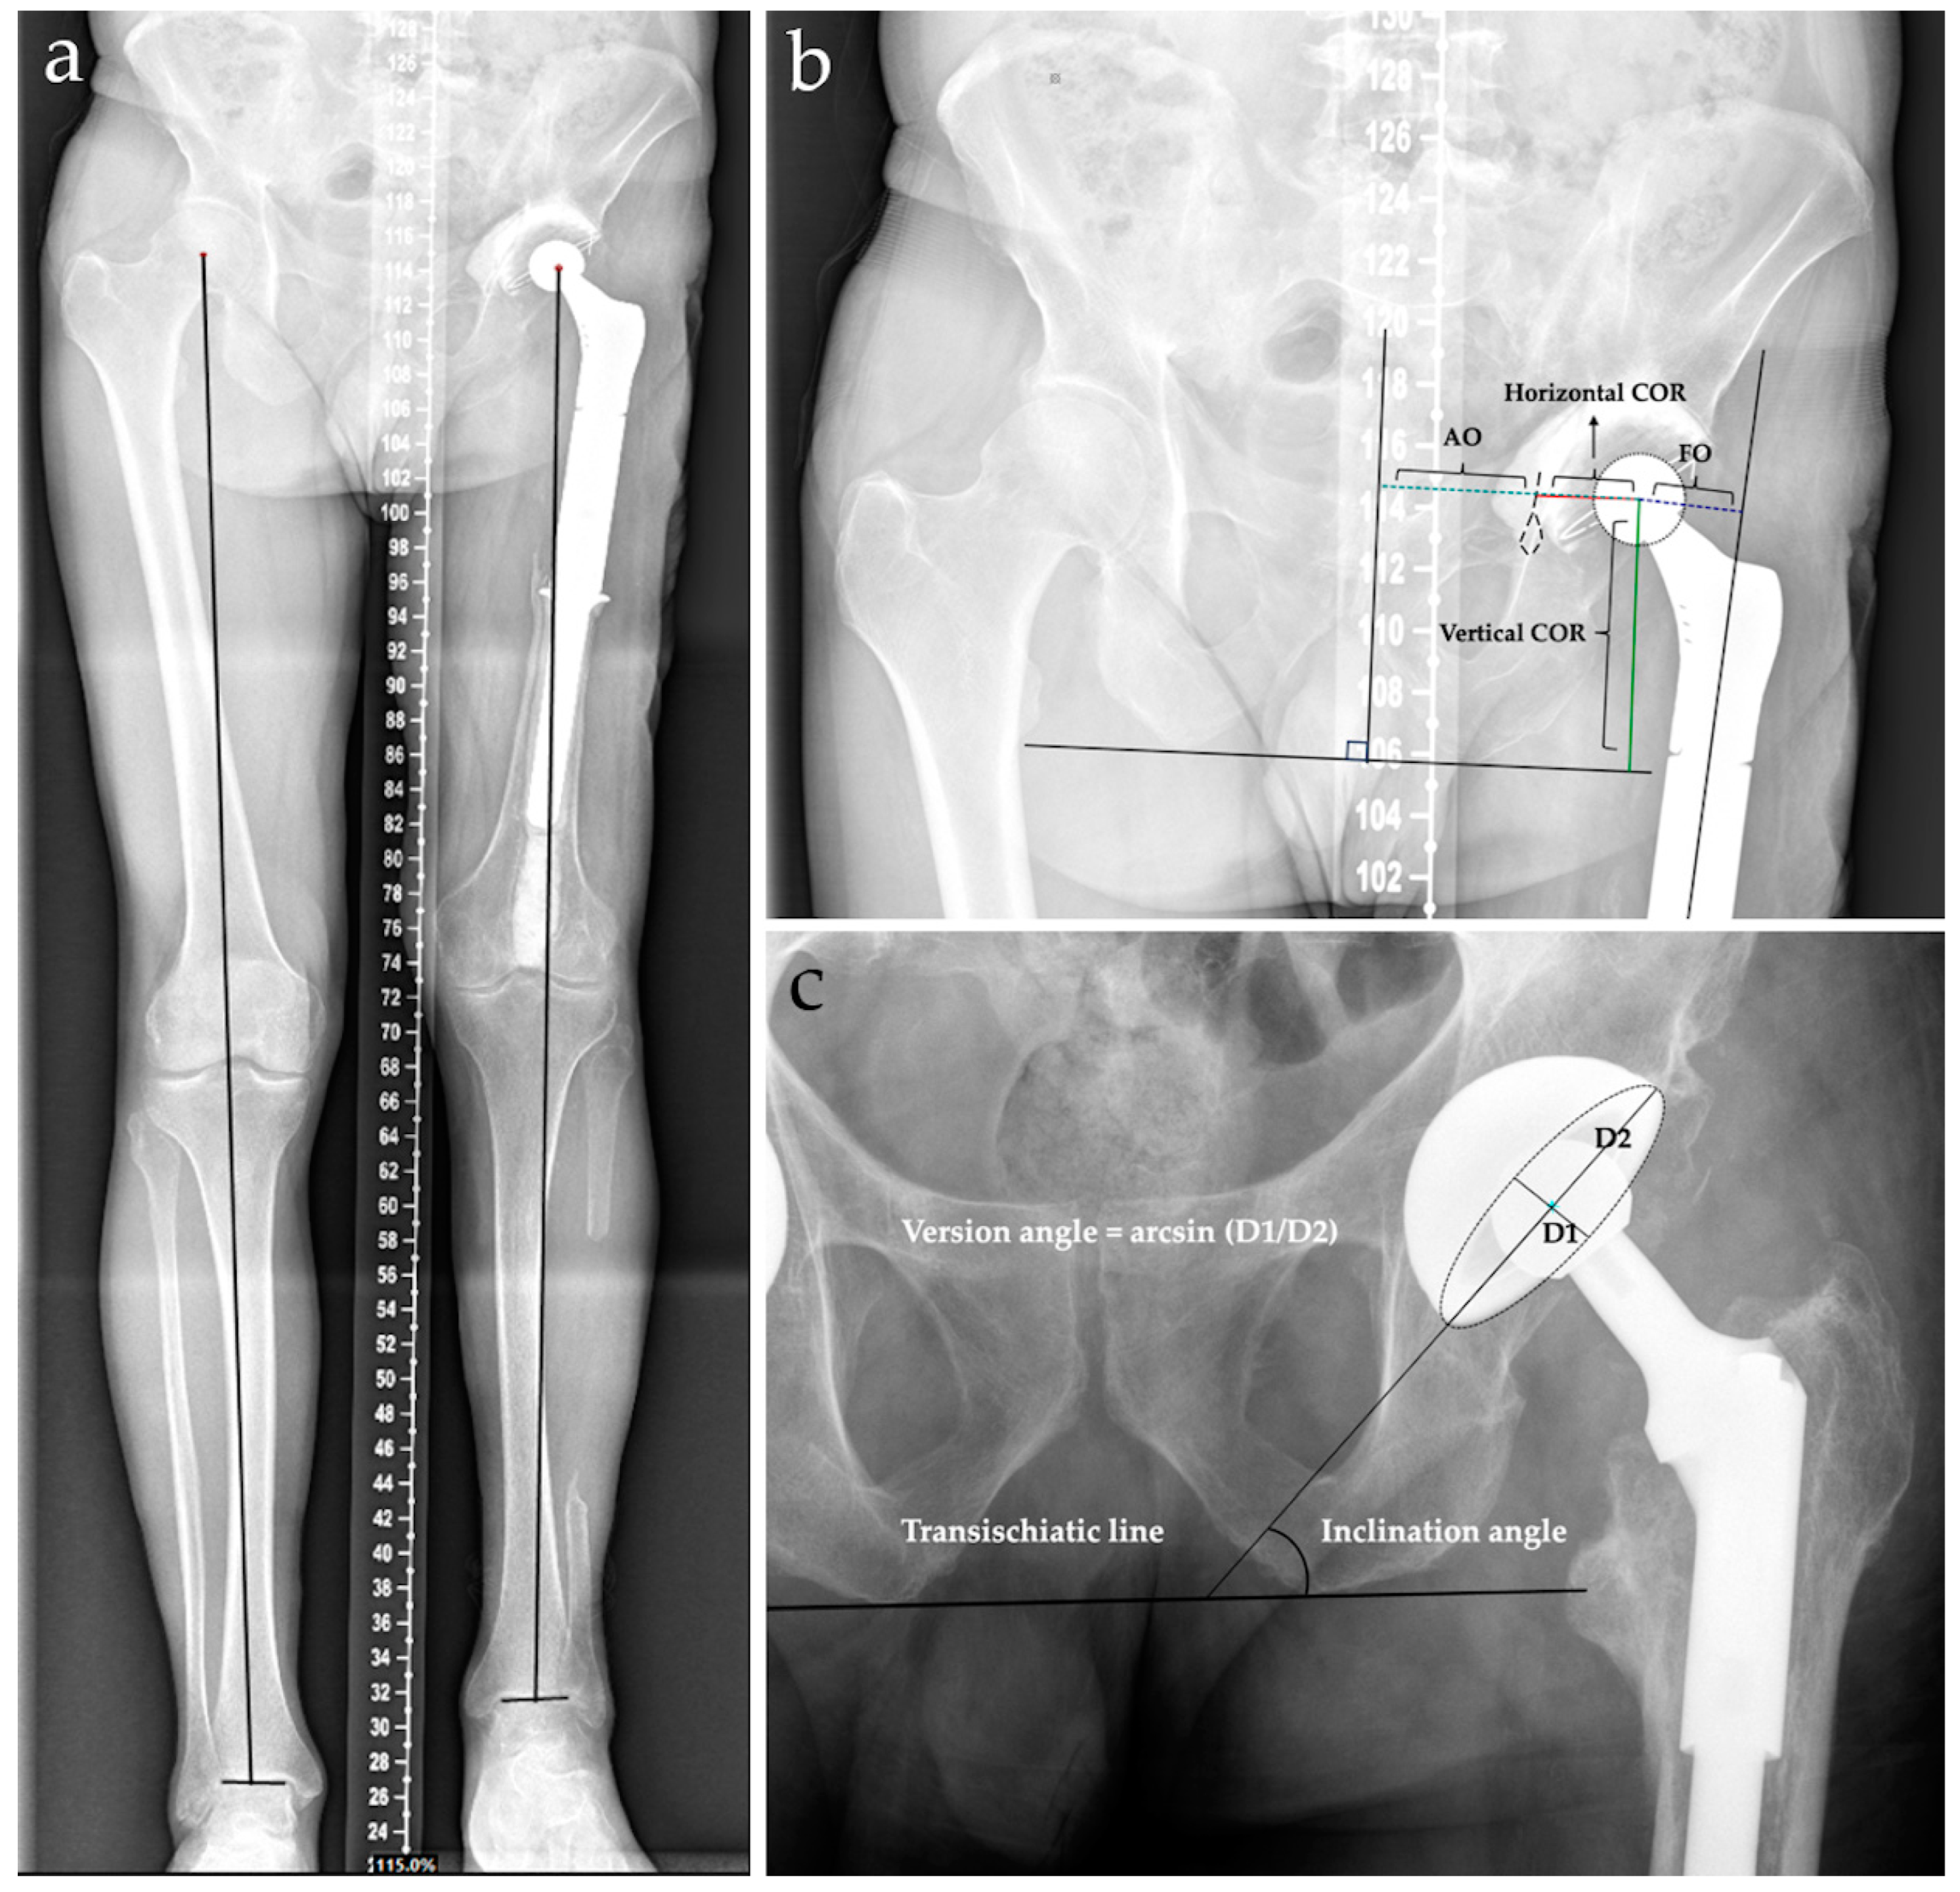

2. Materials and Methods

| AO | Acetabular offset |

| FO | Femoral offset |

| LLD | Limb length dicrepancy |

- Flecher, X.; Ollivier, M.; Argenson, J.N. Lower limb length and offset in total hip arthroplasty. Orthop. Traumatol. Surg. Res. 2016, 102, S9–S20. [Google Scholar] [CrossRef] [PubMed]

- Dragosloveanu, S.; Petre, M.-A.; Gherghe, M.E.; Nedelea, D.-G.; Scheau, C.; Cergan, R. Overall Accuracy of Radiological Digital Planning for Total Hip Arthroplasty in a Specialized Orthopaedics Hospital. J. Clin. Med. 2023, 12, 4503. [Google Scholar] [CrossRef] [PubMed]